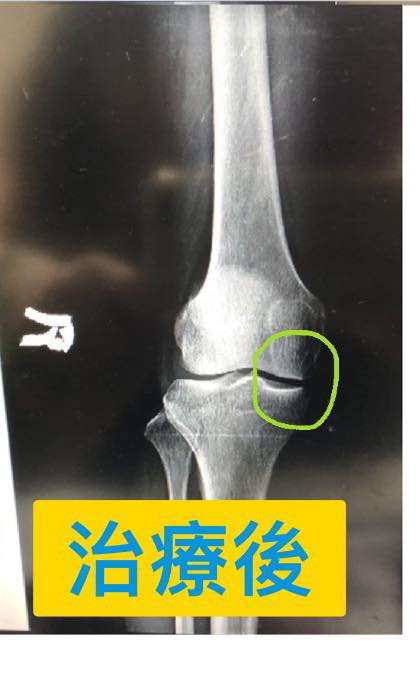

四十多歲的葉小姐抱怨膝蓋疼痛快半年,,最近幾次去跑馬拉松幾乎都跑不完,上下樓梯開始明顯疼痛,就診前拍過X光片可以很清楚的看到膝蓋內側間隙過窄,這大約是退化性膝關節的第二到第三期,經過友人介紹接受膝關節整合治療,大約八週的時間,重新拍片檢查,使用AP VIEW(正位照),兩張照片前後對比可以看到右側膝關節間隙明顯打開,兩張照片脛骨跟腓骨的交會角度幾乎是一樣,股骨跟脛骨的交會角度也是一樣,希望可以排除角度的誤差,不過重點是葉小姐臨床症狀幾乎完全消失!